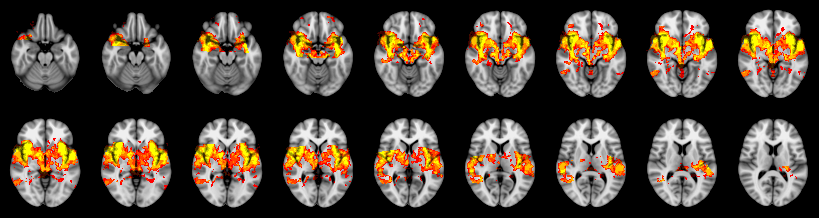

Pain study, TFCE, Uncorrected

Combined

Fisher: